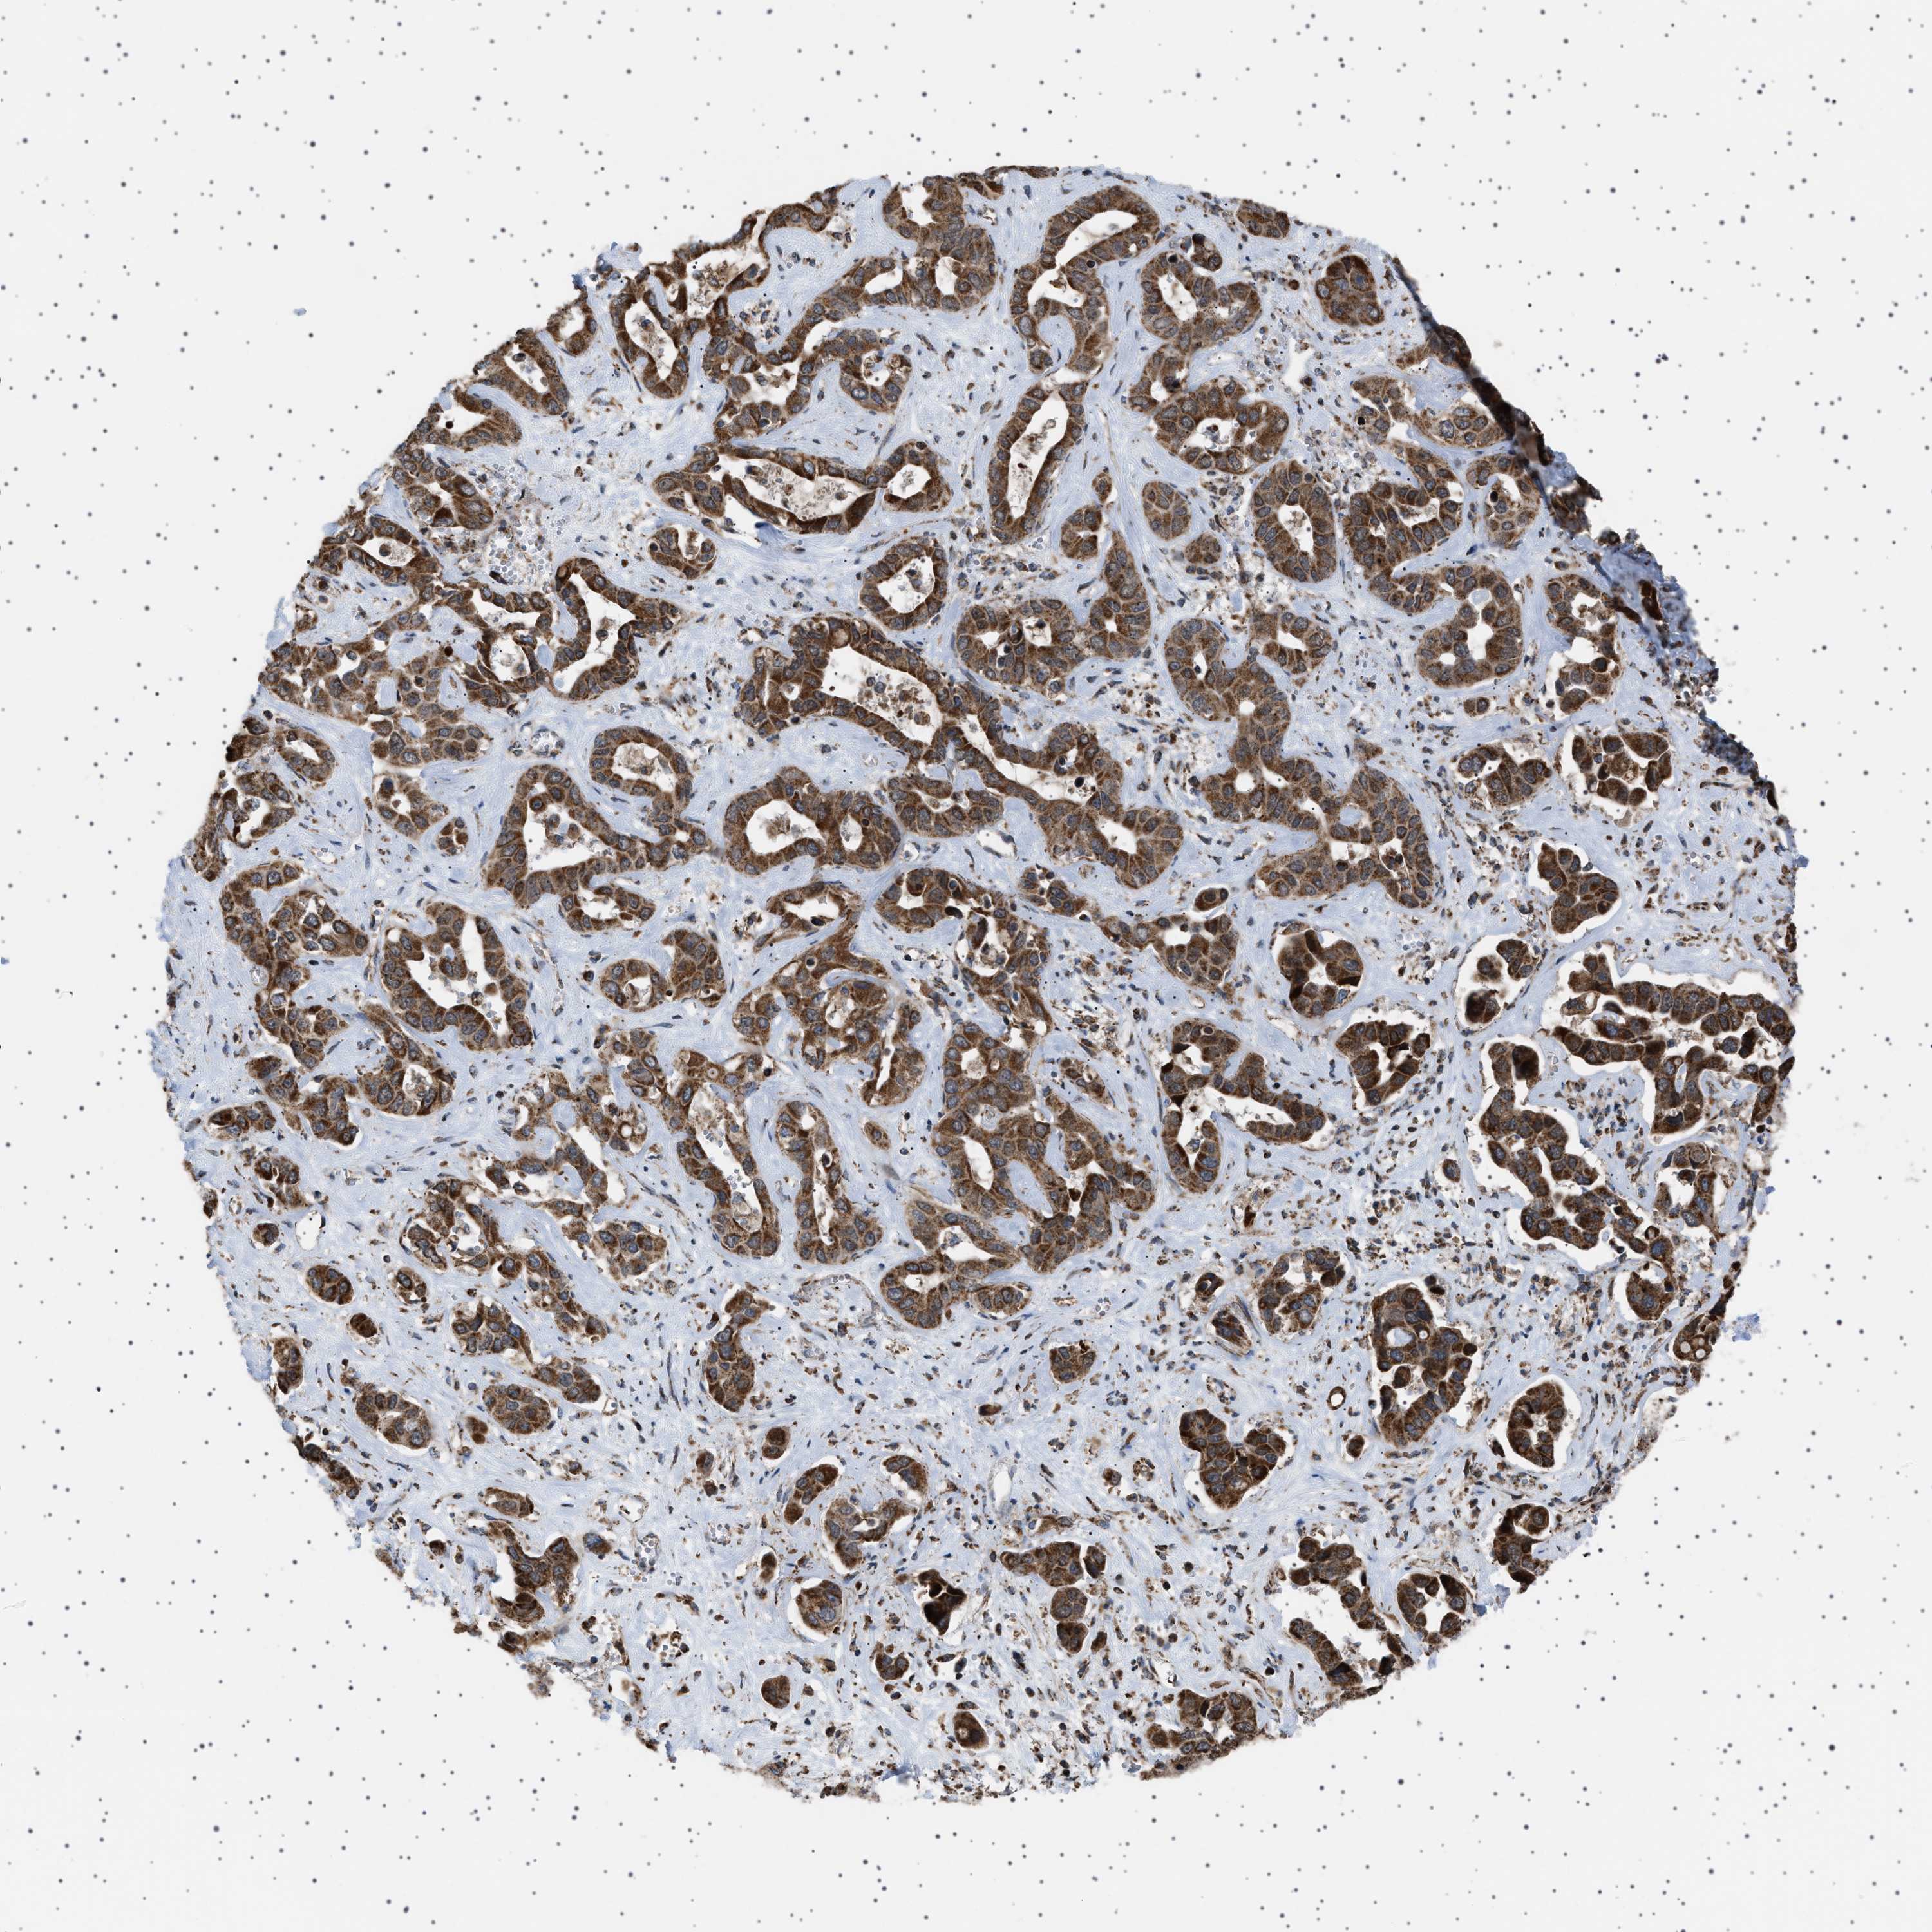

LIVER CANCER - Protein expressioni

A mouse-over function shows sample information and annotation data. Click on an image to view it in a full screen mode. Samples can be filtered based on level of antibody staining by selecting one or several of the following categories: high, medium, low and not detected. The assay and annotation is described here.

Note that samples used for immunohistochemistry by the Human Protein Atlas do not correspond to samples in the TCGA dataset.

Antibody stainingi

Antibody staining in the annotated cell types in the current human tissue is reported as not detected, low, medium, or high, based on conventional immunohistochemistry profiling in selected tissues. This score is based on the combination of the staining intensity and fraction of stained cells.

Each image is clickable and will lead to virtual microscopy that enables deeper exploration of all samples and also displays staining intensity scores, fraction scores and subcellular localization as well as patient and tissue information for each sample.

Antibody HPA017214

Staining

High

Medium

Low

Not detected

Intensity

Strong

Moderate

Weak

Negative

Quantity

>75%

75%-25%

<25%

None

Location

Nuclear

Cytoplasmic/membranous

Cytoplasmic/membranous,nuclear

Cholangiocarcinoma

Carcinoma, Hepatocellular, NOS